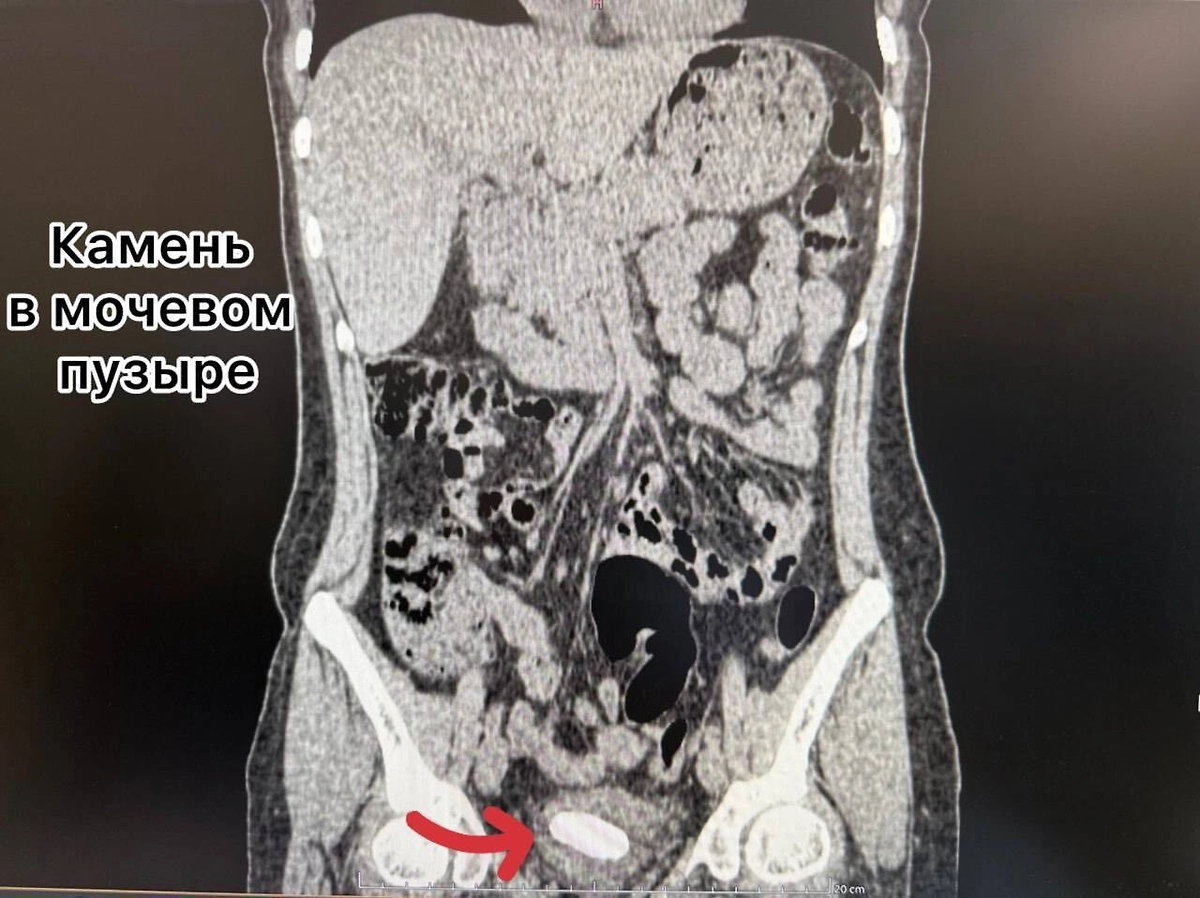

Как оказалось, два года назад женщине установили мочеточниковый стент, но вовремя его не удалили, из-за чего инородный предмет превратился в плотную структуры, а в почке и мочевом пузыре образовались камни. Врачи за раз провели многоэтапную операцию — удалили и стент, и образования в органах.

«Через один минимальный прокол в пояснице (метод перкутанной нефролитотрипсии) с помощью ультразвука был разрушен и удалён почечный камень. Одновременно, через естественные пути, современным лазером Urolase+ Premium был раздроблен и извлечен камень из мочевого пузыря и стент. Операция проводилась с применением эндоскопического оборудования и под рентген-контролем, что гарантировало высочайшую точность», — говорится в сообщении.

Рентген женщины с вросшим стентом во Владивостоке. Обложка © Telegram / Тысячекоечная больница г. Владивосток